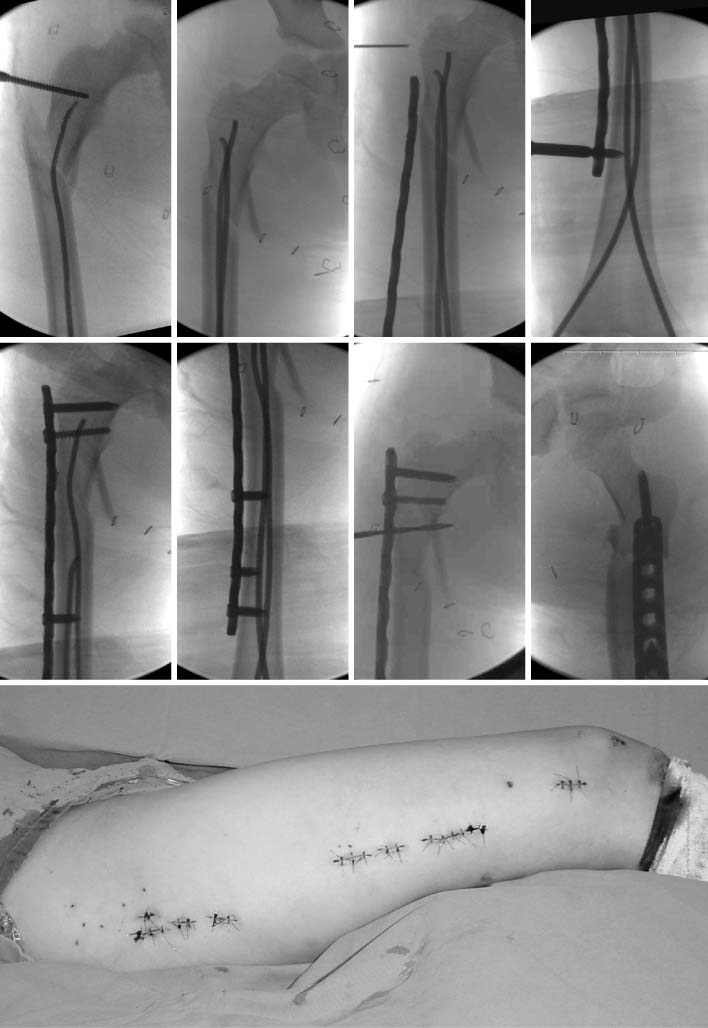

Fig. 5

These are the sequence of operatingprocedure in the suggested patient of Fig. 1. After the temporary reduction of femoral fracture with flexible nails, the plate was introduced through the submuscular tunnel. Then, the locking screws were fixed at the proximal and distal sides of the plate. The fracture site was not open to preserve the biology. The flexible nail makes an easier reduction of fracture, which facilitates the minimally invasive plate osteosynthesis (MIPO) procedure.

Fig. 6

In postoperative films (left), a satisfactory reduction was achieved. The patient had a solid union, on 1 year follow-up films (right).

Fig. 9

In postoperative films (left), a good alignment was achieved. The fracture united at 3 months postoperatively (right).